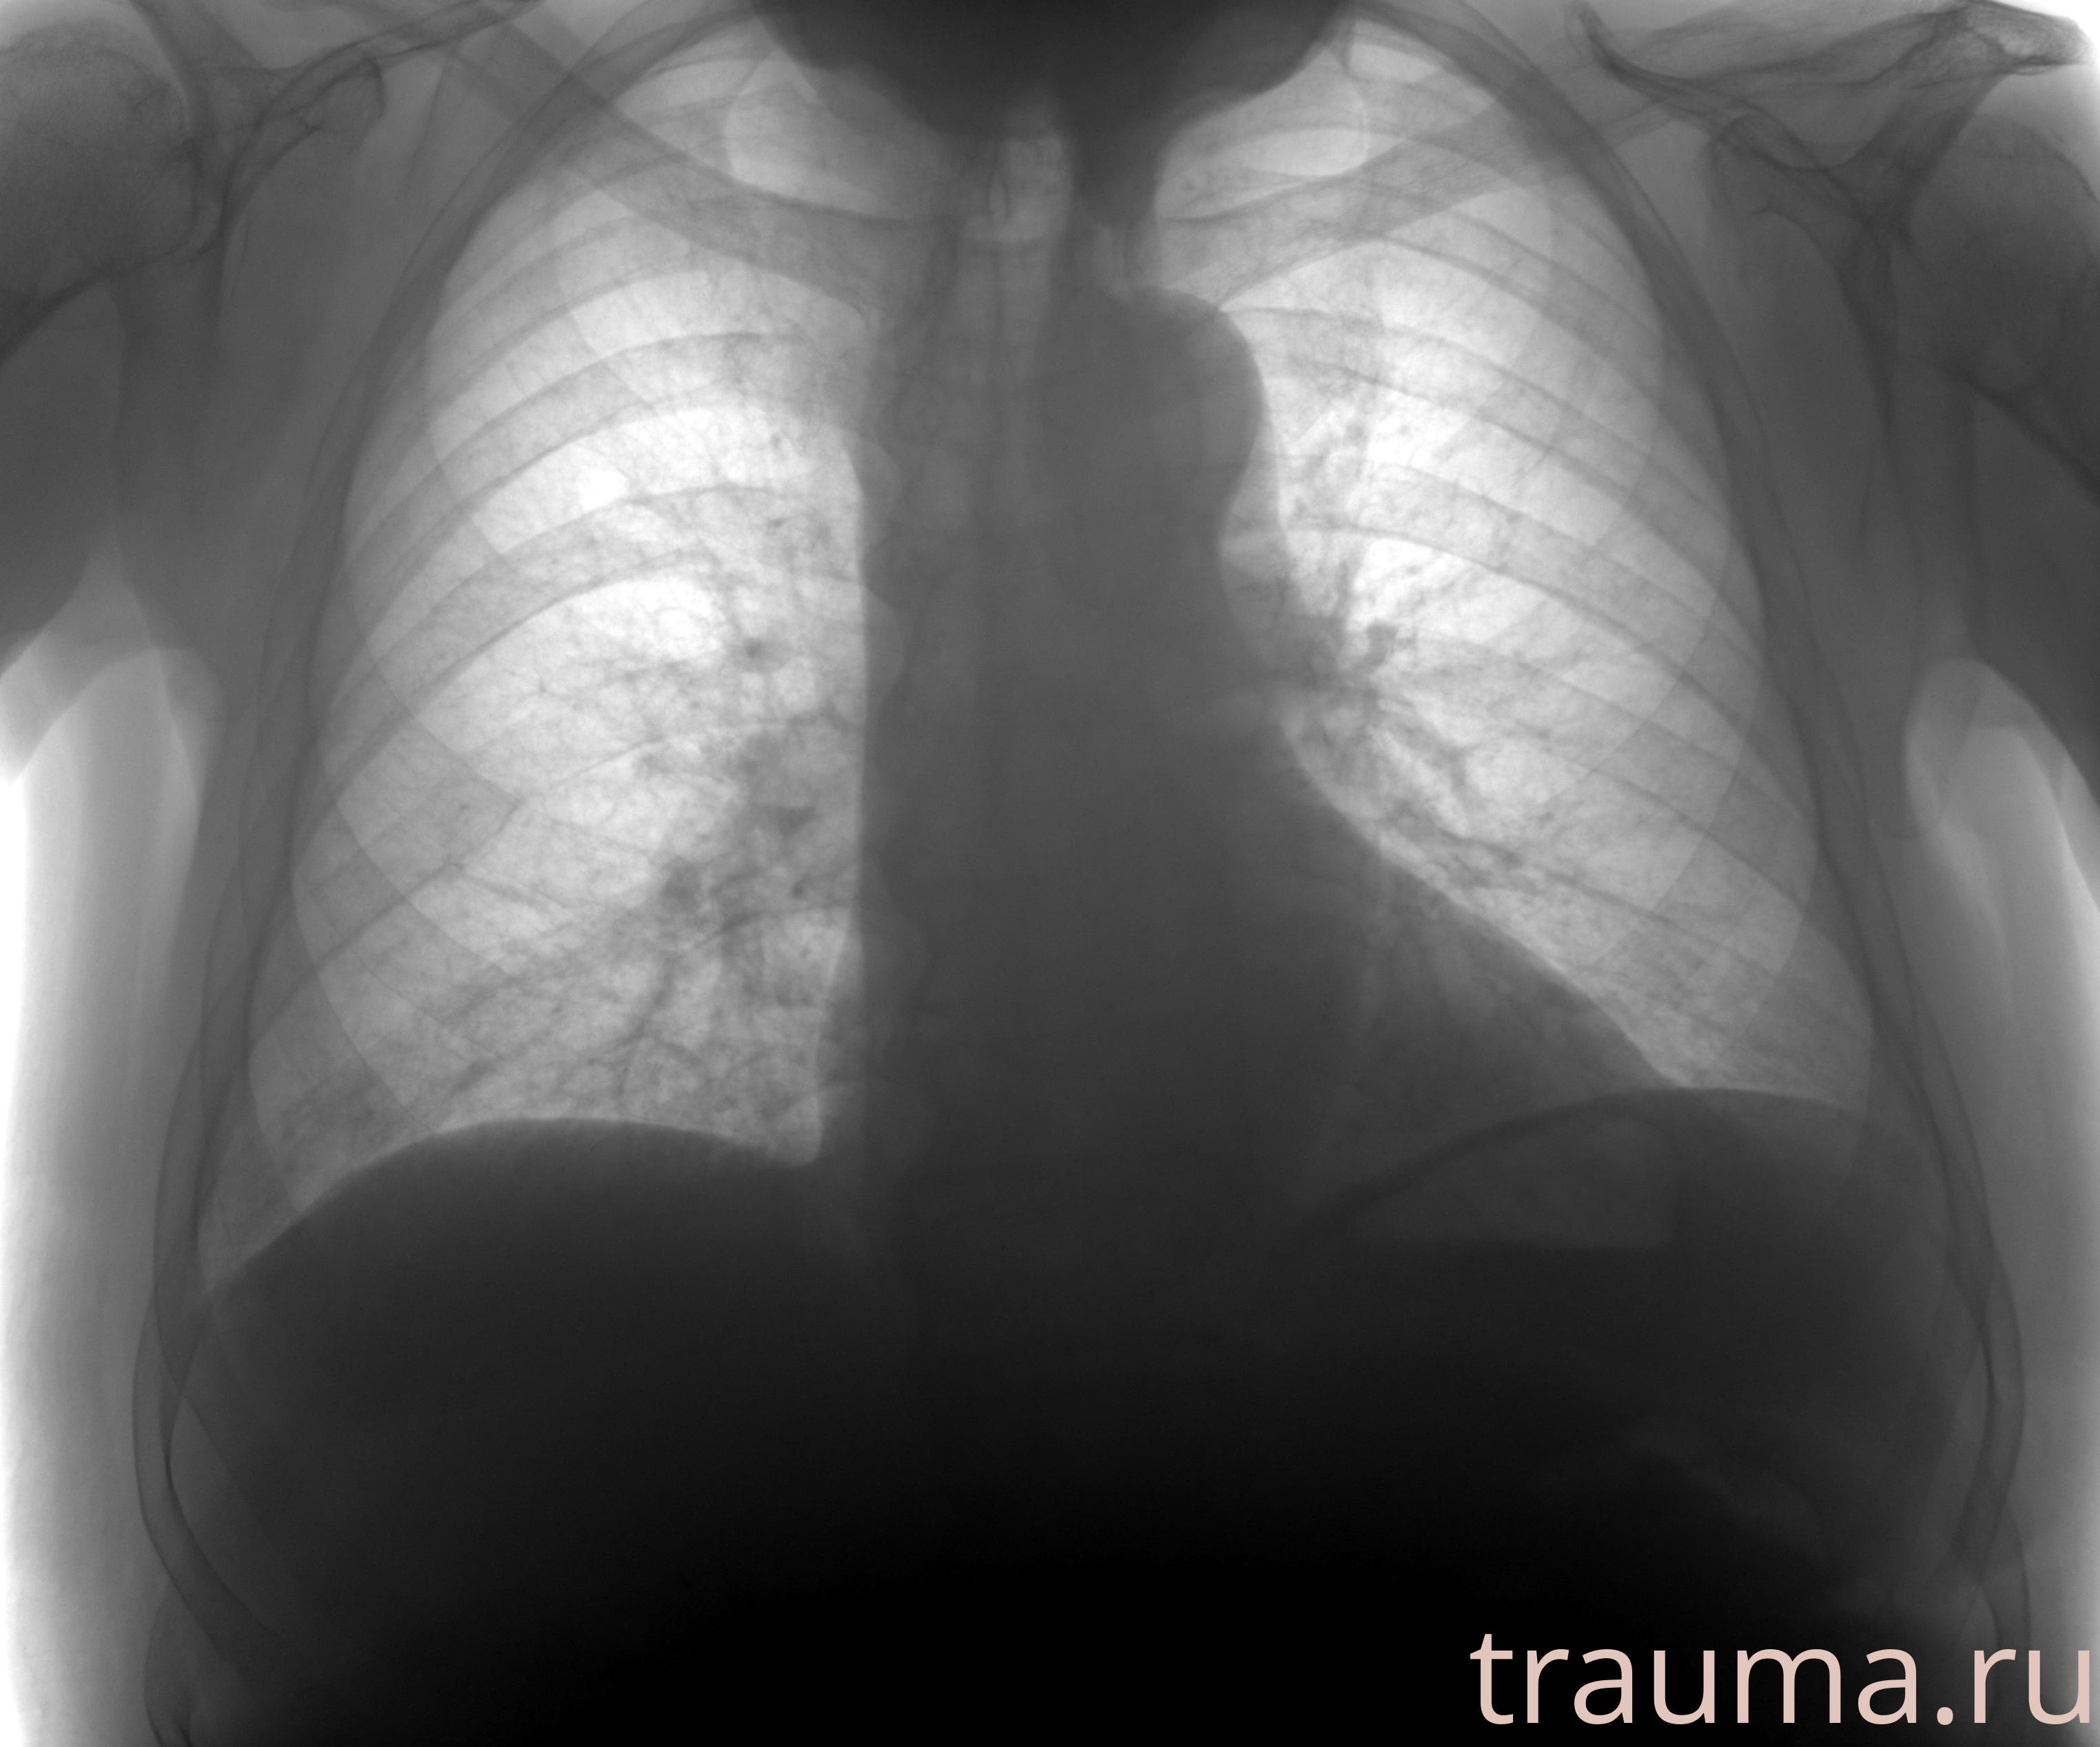

Рентген на дому: по вашему адресу приезжает врач-рентгенолог, травматолог-ортопед с мобильным рентгеновским аппаратом, проводит диагностику травмы или заболевания, делает необходимые рентгенограммы, дает рекомендации по дальнейшему лечению. Получить качественные снимки в домашних условиях возможно благодаря уникальной методике, разработанной МосРентген Центром для института  Склифосовского